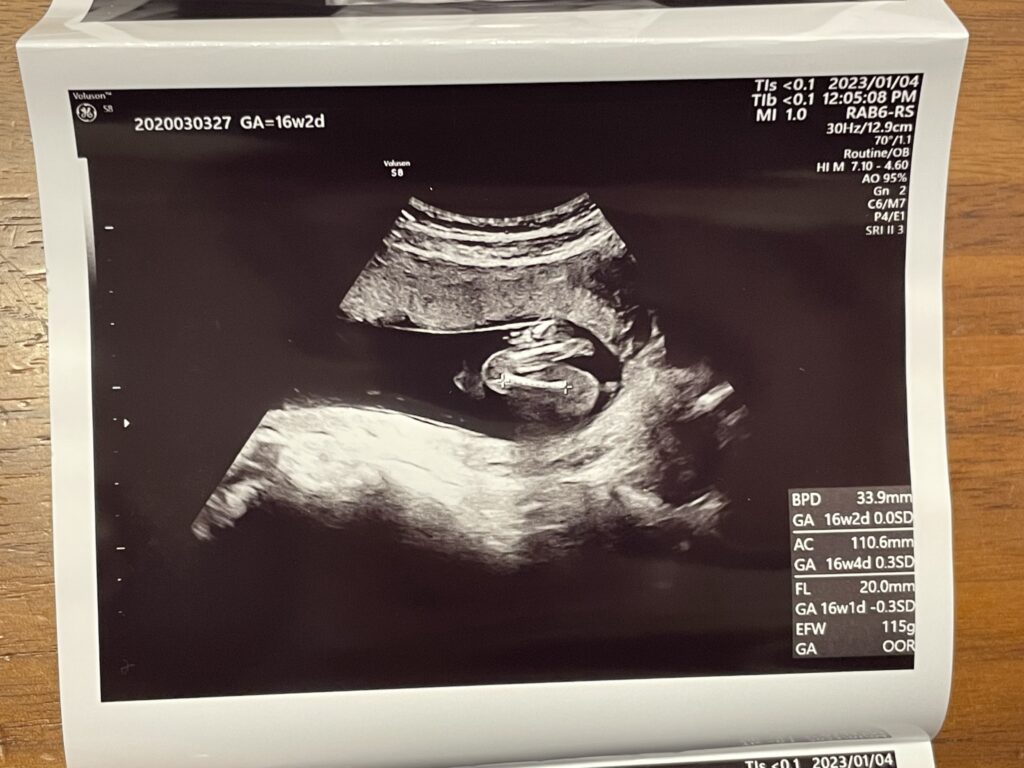

- 経腹エコー(4D)

経腹エコー(4D)

希望したわけではないのですが、お腹からの普通のエコーに加えて途中から4Dに切り替えて見せてくれました。

今日、性別がわかるのかなー?!とドキドキしていたのですが、次回の詳しい超音波検査(スクリーニング検査)の時にわかるとのことでした。